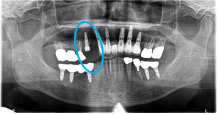

Before

歯根が真っ二つに割れていました

抜いた歯

【抜歯後】

After